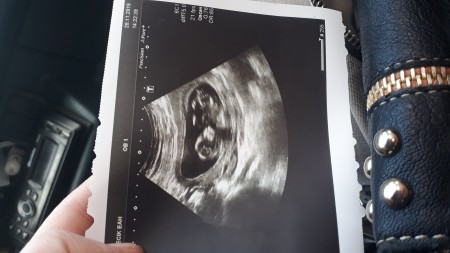

bu foto ikili tarama testindendi

Ay demeyin ya bu foto ciktiktan 2 ay sonraydi sanirim  ayrintili da ultrasona girdim bakar bakmaz kiz dedi aslinda ama devlet hastanesinde bakildi ne bilim tabi oncelik saglik ve hayrli olmasi ama sezeryanli oldugum icin erkek olsaydi kapanisi yapardim oyel belki yanilmislardr felan diye fikrinizi almak istedim

%99 kiz dedi gorur gormez doktor hayirlisi fikirlerinizi aldim devlette bakimdigim icin yanlma olabilir mi acaba diye

Ogrendim ayrintili ultrasonda  kizmis aslinda ama devlet hastanesinde girdim ayrintilu ultrasona renkli felan degildi yani dedim belki yanilmistr doktor

Ilk kizimda ozelde girmistim herseyini bende anlayabiliyordum ama bunda yok goremedim bisey